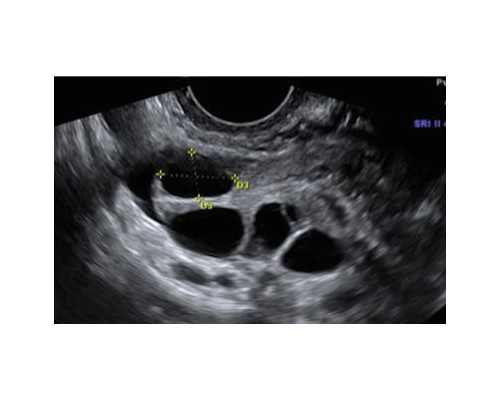

这两款国内外都买的比较火,你们可以喜欢那个就用那个,我们所说的舒适无感,并不是阴道完全感觉不到月亮杯的存在,阴道的三分之处是没有感觉的,靠近宫颈越近是越有感觉,所以我们在使用月亮杯的时候能感觉杯底和杯尾,只不过硅胶柔软,所以身体不会感觉难受。使用过的女性更有权力发表感受。比较直观的对比就是使用直筒的月亮杯宫颈感受会加重,会有种杯子没有完全打开的错觉,使用异形的月亮杯,完全贴合宫颈,不会有杯子未打开的错觉。具体月亮杯放置的正确位置,如下图,既不要放到最里面,也不要放在宫颈处。如图